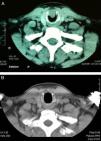

We describe the case of a 50-year-old man who attended due to a three-month history of progressive dyspnoea on moderate and heavy exertion, with mild inspiratory stridor. A history of previous intubation due to two collarbone surgeries two years previously was noted. Nasofibrolaryngoscopy showed a right anterior subglottic lesion; its extension was determined by computed axial tomography (CT) (Fig. 1A). Rigid bronchoscopy and laser resection (Neodymium-YAG) was scheduled; during surgery, biopsies were taken and partial vaporisation of the lesion was performed. The histopathological result was consistent with a pleomorphic adenoma, so subglottic resection was carried out using an open approach in a second surgical procedure: the trachea was exposed with an incision over the second ring, similar to a tracheotomy; cricothyroid membrane incision; vertical connection of the left side of both incisions (cricoid arch and tracheal ring section), lifting a flap to visualise the lesion directly (15cm in diameter, situated along the inside of the cricoid arch up to the height of the upper border of the first tracheal ring). Tumour excision was completed with partial cricotracheal resection (cricoid arch and anterior portion of the first tracheal ring). The defect was closed by primary reconstruction with sternothyroid muscle plasty over a Montgomery silicone T-tube (8mm) and layered wound closure. After five days, the patient was discharged with mild-moderate cervical subcutaneous emphysema, which persisted for five weeks, odynophagia, requiring a soft diet for one month, and dysphonia due to the placement of the upper rim of the stent on the vocal cords. The definitive histopathological study was a benign salivary gland tumour, consistent with basal cell adenoma (monomorphic adenoma), with clear margins. The T-stent was removed after four months. Vocal granulomas were detected, which disappeared in two weeks after treatment with oral prednisone (30mg in tapered dosage), and the voice returned to normal. The case has been monitored by nasofibrolaryngoscopy and radiological follow-up (Fig. 1B) for the last 1.5 years, with no evidence of recurrence to date.